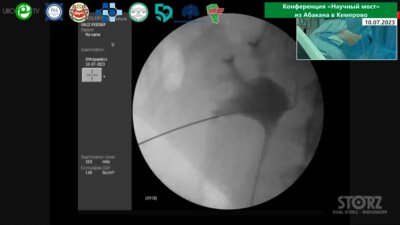

Россия, Абакан-Кемерово

07-10 июл 2023